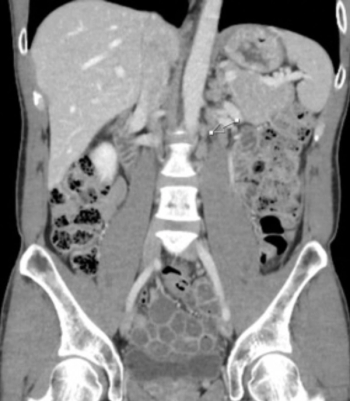

The clinical quandary by Langer et al discusses a contralateral late relapse of the original right nonseminomatous germ cell tumors.